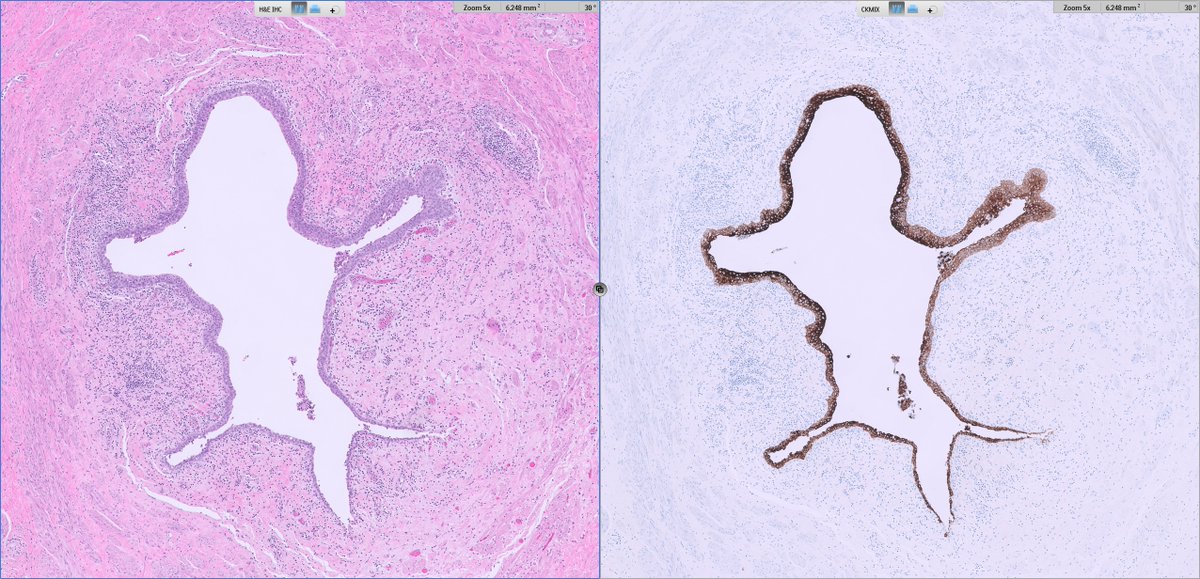

Histopathology 🔬

Architecture: grossly nodular tumors, but with infiltrative borders and “honeycomb” spread through subcutaneous fat and skeletal muscle.

Cytology: ovoid/epithelioid cells in cords, nests or solid sheets within dense collagenous stroma; mitotic activity usually low in hypocellular areas, higher in more solid/anaplastic foci.

Special patterns: perineurioma‑like areas (bland spindle cells in whorled/loose‑storiform pattern), fibroma‑like zones (very dense collagen with sparse cells), and foci of small round or rhabdoid cells in recurrences/metastases.

Additional findings: thin‑walled vessels (sometimes hemangiopericytoma‑like); typical absence of alternating fibromyxoid zones and classic collagen rosettes of LGFMS.

Immunohistochemistry 🧫

Positives:

EMA (diffuse or focal)

YAP1 (N‑ and C‑terminal)

Cyclin D1 in most cases

CD34 and SMA may be focally positive

Negatives:

MUC4 consistently negative (key point against classic SEF/LGFMS)

S100, SOX10, desmin, STAT6, most endothelial markers in typical cases

⚠️Notes:

Some tumors show strong ERG/CD31/D2‑40 and TFE3 expression, closely mimicking epithelioid hemangioendothelioma; in such cases, documentation of YAP1–KMT2A fusion and molecular clustering are crucial for correct classification.